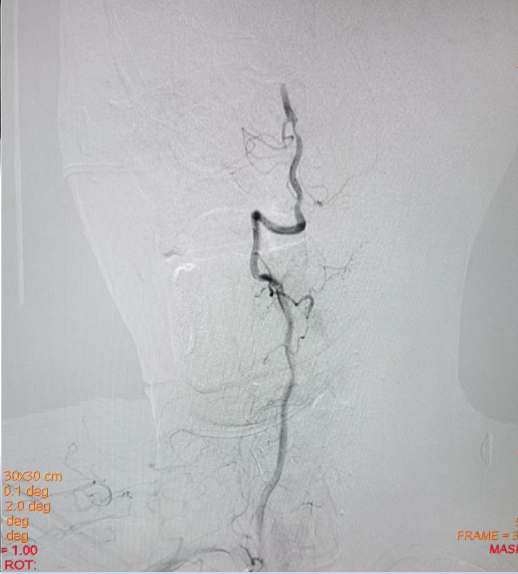

左侧椎动脉起始部成形

病历夹什么径技·第152期|串联营病历夹:川陕大营_https://www.jmylbn.com_新闻资讯_第21张

病历夹什么径技·第152期|串联营病历夹:川陕大营_https://www.jmylbn.com_新闻资讯_第22张

<<滑动查看下一张图片>>

确认血栓远近端

病历夹什么径技·第152期|串联营病历夹:川陕大营_https://www.jmylbn.com_新闻资讯_第23张

血管再通后造影

病历夹什么径技·第152期|串联营病历夹:川陕大营_https://www.jmylbn.com_新闻资讯_第24张

血管再通及左椎支架植入

病历夹什么径技·第152期|串联营病历夹:川陕大营_https://www.jmylbn.com_新闻资讯_第25张

病历夹什么径技·第152期|串联营病历夹:川陕大营_https://www.jmylbn.com_新闻资讯_第26张

病历夹什么径技·第152期|串联营病历夹:川陕大营_https://www.jmylbn.com_新闻资讯_第27张

左椎支架植入后造影

病历夹什么径技·第152期|串联营病历夹:川陕大营_https://www.jmylbn.com_新闻资讯_第28张